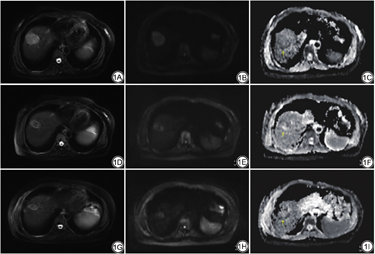

治疗前后AFP、形态学参数(最大长径、面积、体积)和MRI功能学参数(ADC、SER)配对Wilcoxon秩和检验(非参数配对)结果显示,治疗后HCC形态明显缩小,AFP明显减低;同时,SER均明显减低、而ADC值明显增高(P均<0.05),详见表3、图1。

重离子治疗前后肿瘤形态、ADC值及AFP变化

Size, ADC value and AFP comparison of HCC before and after heavy-ion therapy

| 变量 | 治疗前 | 治疗后3~6个月 | Z值 | P值 |

|---|---|---|---|---|

| 形态学参数 | ||||

| 面积/cm2 | 11.60(4.70,27.50) | 5.17(0.97,19.00) | -4.457 | <0.001 |

| 体积/cm3 | 39.45(10.02,150.65) | 11.37(2.62,81.70) | -4.305 | <0.001 |

| AFP/(IU•mL-1) | 134.00(14.50,1000.00) | 40.90(9.11,574.50) | -3.260 | 0.001 |

| MRI功能学参数 | ||||

| ADC/(mm2•s-1) | 1.20(1.02,1.78) | 1.47(1.22,1.78) | -3.543 | <0.001 |

| 动脉期T1WI信号强化率/% | 0.47(0.05,0.86) | 0.09(0.00,0.50) | -3.473 | 0.001 |

| 门脉期T1WI信号强化率/% | 1.04(0.83,1.56) | 0.65(0.17,0.98) | -4.217 | <0.001 |

| 静脉期T1WI信号强化率/% | 0.97(0.54,1.34) | 0.55(0.08,1.05) | -2.693 | 0.007 |

注:ADC为表观扩散系数;AFP为甲胎蛋白;HCC为肝细胞癌。数据以中位数(四分位间距)格式表示。